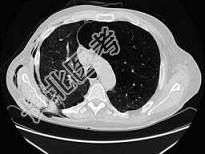

- 单项选择题男,68岁, 胸闷、气短1年余,加重1周, 右胸有手术史,结合CT图像, 最可能的诊断是 ( )

A、右侧气胸并皮下气肿、左侧肺气肿

B、右侧气胸并皮下气肿、左侧肺不张

C、双侧肺气肿

D、右侧气胸并皮下气肿

E、右侧肺间质病变、左侧肺气肿